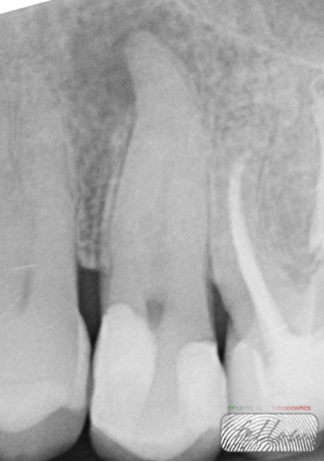

Fig. 2

The X-ray shows the presence of a periapical lesion on tooth 25. Pulp vitality and electric tests were negative.